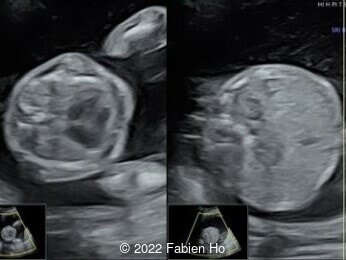

Case Report: A 23-year-old G5P4 woman from Mayotte with no past history presented at 22 weeks gestation. The Down syndrome screening was 1 in 900 and subsequent fetal cDNA exam was normal. The mother's serologies were positive for Rubeola, though negative for Toxoplasmosis and Syphilis. The male fetus was found to have intrauterine growth restriction and the following findings:

A CT scan was subsequently performed at 32 weeks gestation

Characteristics of osteogenesis imperfecta that can be identified prenatally include early onset of severe long bone shortening and bowing due to multiple intrauterine fractures, narrow thorax, normal head circumference but abnormal translucency and compressibility [8,9]. The poor mineralization of the skull leads to deformation of the head by the ultrasound transducer [10]. The diagnosis can be made as early as the first to early second trimester [11]. Several cases have also been documented in the literature that associate osteogenesis imperfecta with an increased nuchal translucency in the first trimester [12].